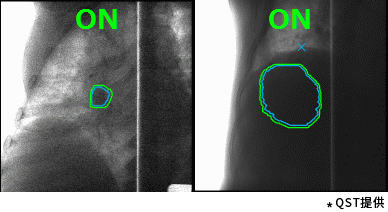

東芝的重離子癌癥放射治療系統具有高速3D掃描,患者自動定位,小型化重離子旋轉機架(搭載東芝自研超導磁鐵實現重量和體積的大幅縮小)等差異化技術。實時成像的呼吸門控是照射技術與重復掃描技術的結合,能夠對伴隨呼吸運動的腫瘤進行快速、準確的照射,且保證劑量分布均一性。特別是,東芝憑借自身先進的超導技術的加持,使旋轉機架得以逐漸小型化。這一成果直接推動了重離子旋轉機架的商業化普及。應用旋轉機架治療,可從360度任意角度進行照射,避開正常組織和危及器官。治療過程中一次定位,避免了移動患者造成的內部臟器位移,實現精準治療,同時提高治療效率,增加治療人數,在同類型產品中獨具技術優勢。

高速掃描+呼吸門控照射(動圖)